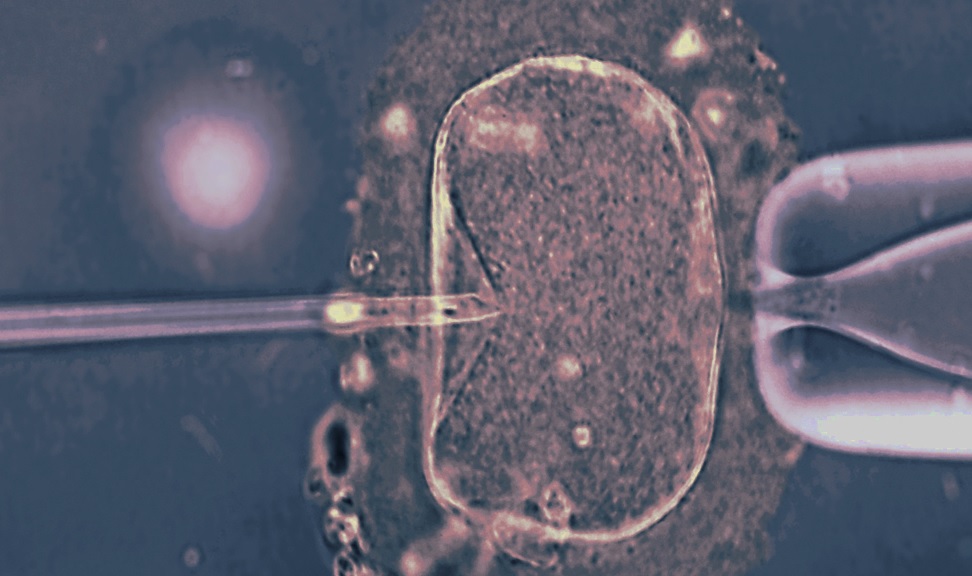

Metoda projedrne transplantacije, ki so jo raziskovalci in raziskovalke preučevali, se v prvi fazi ni razlikovala od običajne umetne oploditve. Najprej so torej v jajčece matere vnesli jedro moške spolne celice. Približno osem ur zatem, še preden bi se celica prvič imela možnost deliti, pa so jedro celice izsrkali iz oplojenega jajčeca, ki je vsebovalo obolele mitohondrije. Jedro z DNK obeh staršev so na koncu vnesli v jajčece donatorke z zdravimi mitohondriji.